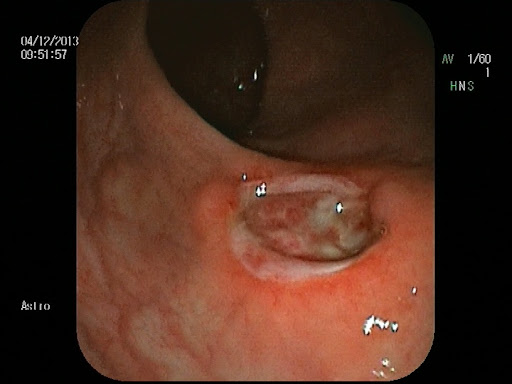

Клиническая картина перианальных кондилом может быть разнообразной, а на начальных этапах заболевание часто протекает бессимптомно. Разрастания могут быть единичными или множественными, плоскими или на тонкой ножке, напоминая по форме цветную капусту или петушиный гребень. Цвет новообразований варьируется от телесного до розового или коричневатого.

- Осмотр и пальпация. Врач-проктолог проводит визуальный осмотр аногенитальной области для оценки количества, размера, формы и локализации кондилом.

- Аноскопия. Это инструментальное исследование, при котором с помощью специального прибора (аноскопа) осматривается слизистая анального канала на глубину до 8–10 см. Процедура необходима для выявления кондилом, расположенных внутри заднего прохода, которые не видны при наружном осмотре.